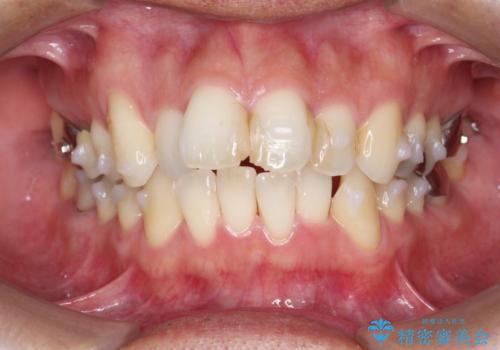

- 突き出た前歯の角度の改善と虫歯治療の改善を求めて来院されました。

虫歯を除去したのち、マウスピース矯正治療を行い、歯並びやがたつきを改善したのち、セラミックに置き換えることで審美性の向上を計画します。